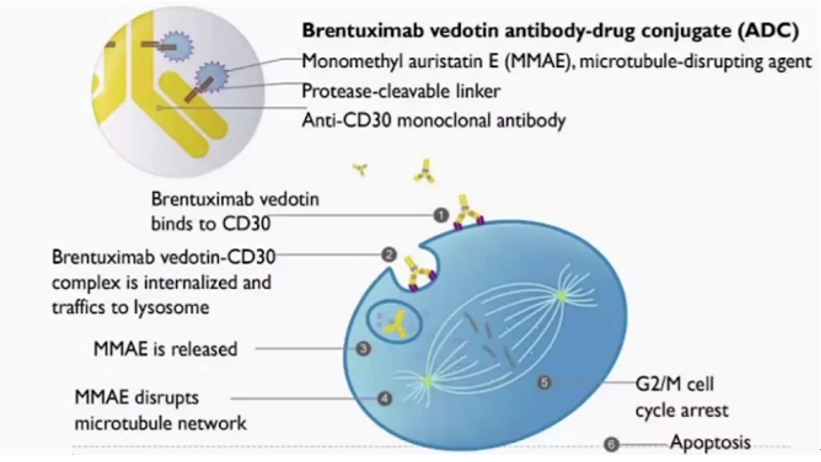

原发性纵隔大B细胞淋巴瘤(PMBL)通常发生在年轻人群中,以前纵隔肿块为特征。临床上发现,部分非纵隔部位发生的淋巴瘤也具有PMBL的基因表达特征;关于这些肿瘤如何...

为进一步提高我国淋巴细胞疾病的整体诊疗水平,第六届上海国际淋巴肿瘤高峰论坛暨第二届血液转化和创新论坛于2021年6月25日至27日在上海召开。在本次大会上,吉林大...

2021年6月9日-17日,第26届欧洲血液学年会(EHA 2021)以线上会议的形式召开。作为欧洲血液学领域规模最大的国际会议,每年都有来自全球100多个国家的...